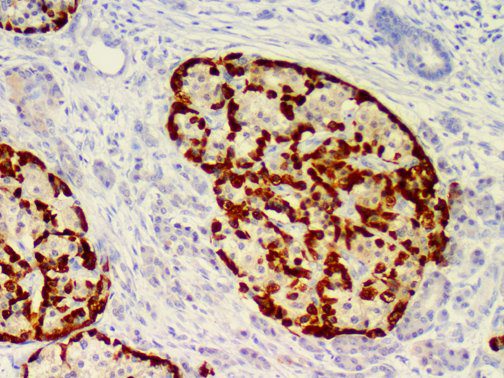

It is the ICU physician who is most likely to witness one of the deadliest manifestations of the abnormal immunological response, the cytokine storm syndrome (CSS). This response is also referred to by some as the cytokine release syndrome (CRS). CSS is characterized by continuous activation and expansion of macrophage and lymphocyte populations, which secrete large amounts of cytokines, causing the cytokine storm. This massive cytokine release is akin to hemophagocytic lymphohistiocytosis (HLH) disease, a syndrome characterized by initial unchecked and persistent activation of cytotoxic T lymphocytes and NK cells.

Clinical and laboratory manifestations of HLH include fever, enlarged liver and/or spleen, neurologic dysfunction, coagulopathy, liver dysfunction, cytopenias (i.e., low levels of erythrocytes, leukocytes, and/or platelets), hypertriglyceridemia, hyperferritinemia, hemophagocytosis, and eventually diminished NK cell activity as the immune system becomes progressively paralyzed. HLH can be familial (primary HLH) or secondary to another disease process (sHLH), such as rheumatic disease, in which it is referred to as macrophage activation syndrome (MAS, characterized by elevated ferritin).